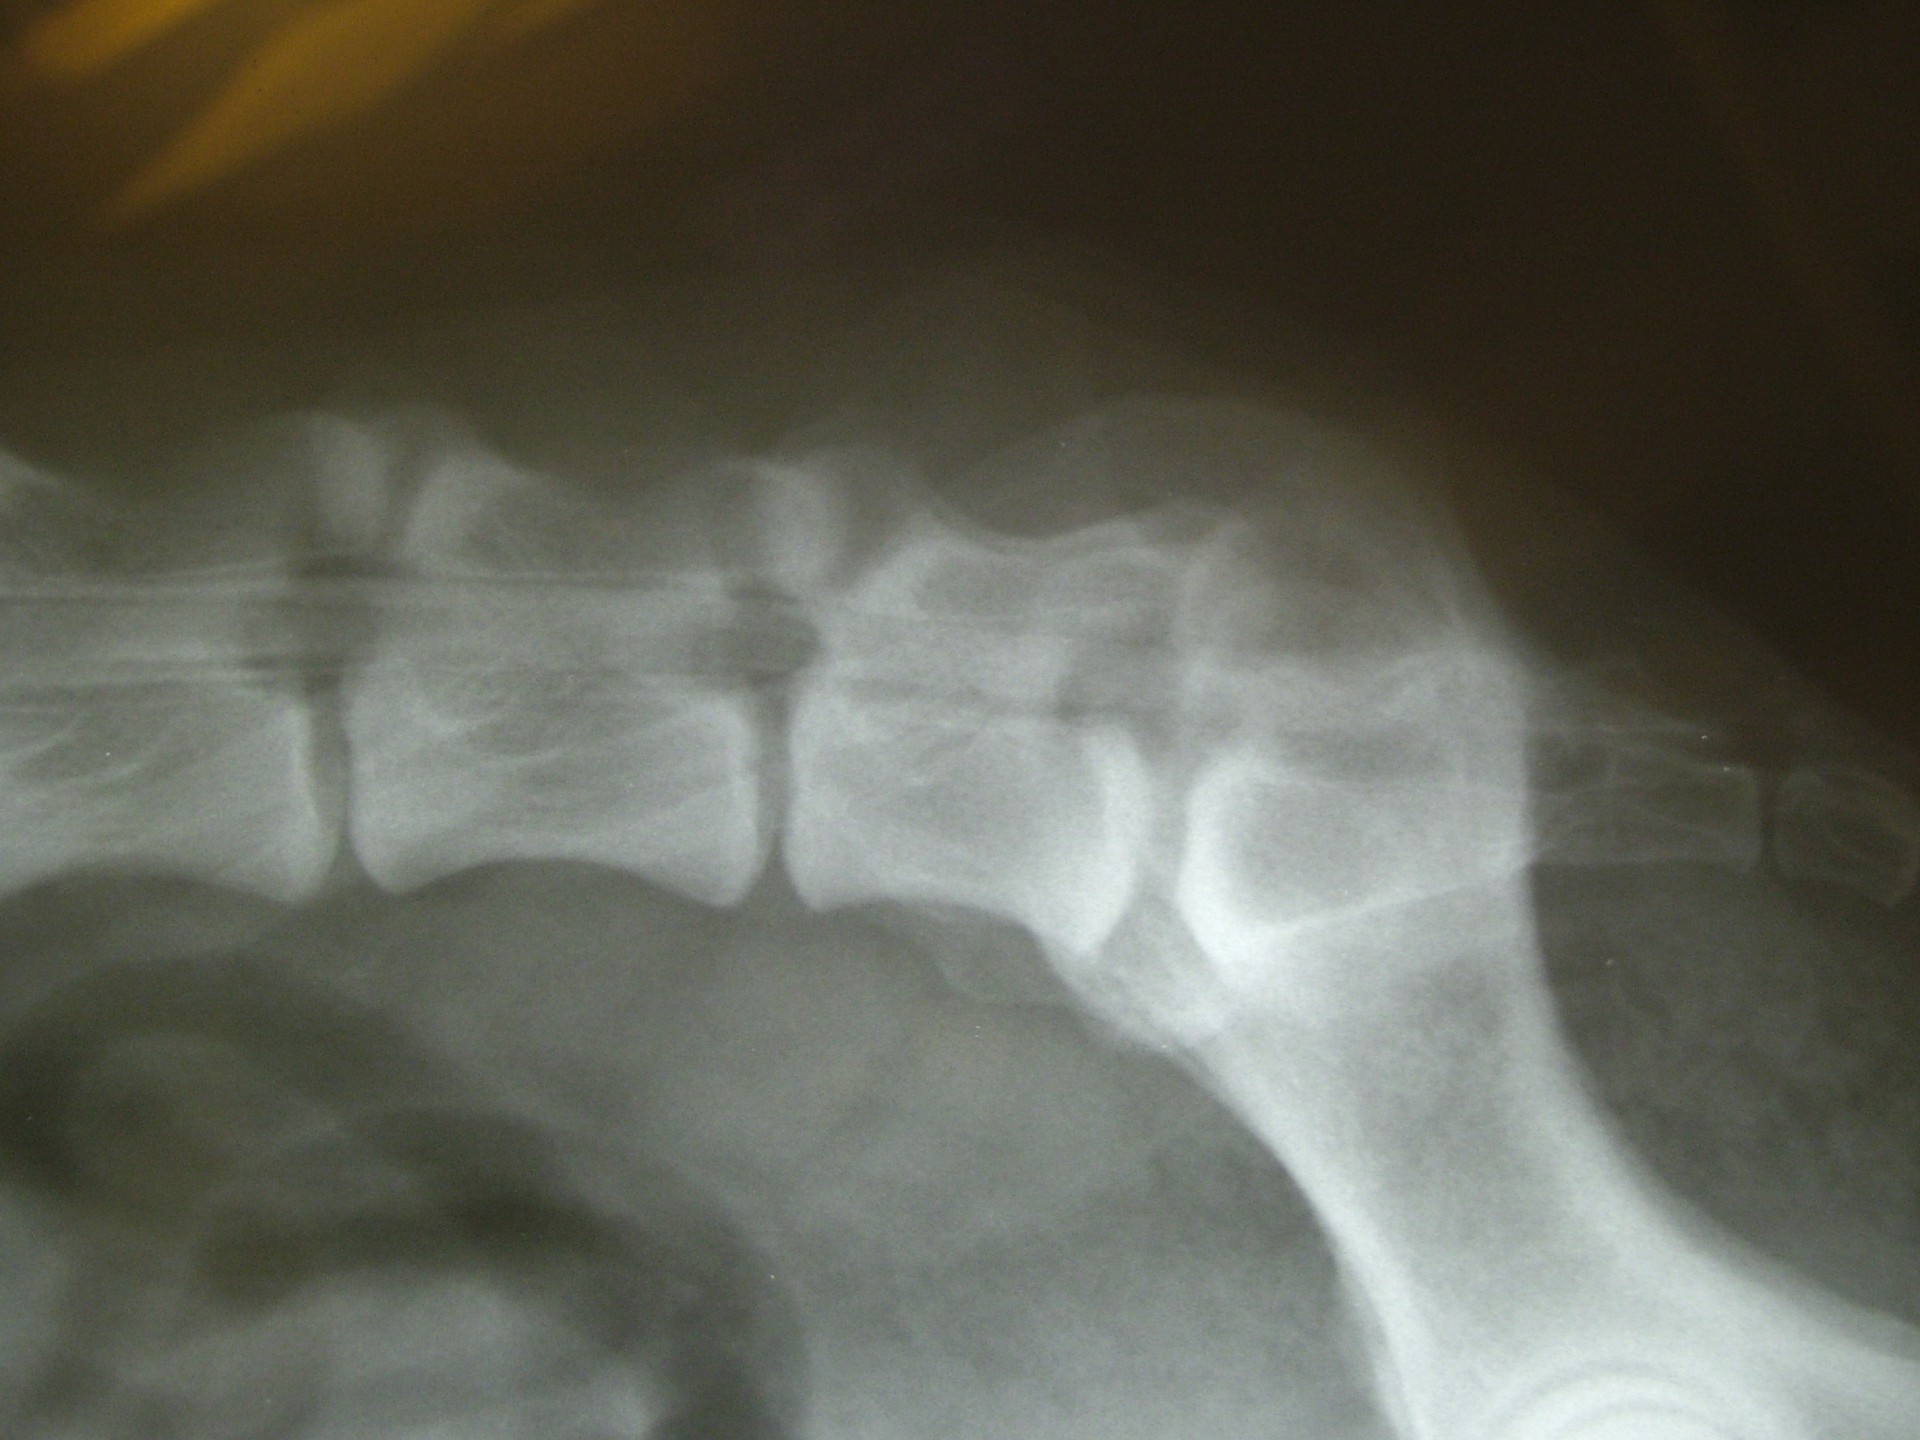

A C.E.C diagnosztikájának legfontosabb lépése a kórelőzmény megismerése után (hátulsó testfél gyengeség, rogyadozás, széklet-vizeletürítési problémák, fájdalom stb.) az alapos klinikai vizsgálat, mely során a gerinctájék fájdalmasságát, a hátulsó végtag reflexeit, a fájdalomérzet meglétét vizsgáljuk.Amennyiben a klinikai tünetek indokolják kiegészítő vizsgálatként elsősorban a röntgenvizsgálat jön szóba, mely során a gerincoszlop ezen szakaszáról oldalirányú felvételt készítünk.

Amennyiben a klinikai tünetek és az oldalirányú röntgenfelvétel alapján a C.E.C. alapos gyanúja felmerül további vizsgálatokkal kell kizárnunk egyéb gerincbetegségeket ill. megerősíteni a C.E.C. diagnózisát.

Az egyik ilyen vizsgálat a gerincfestés vagy myelographia, mely során a gerincvelőt körbevevő térbe (subduralis tér), az agy-gerincvelői folyadékba (liquor) röntgenkontraszt anyagot juttatunk és sorozatos felvételekkel ellenőrizzük annak áramlását. Ennek előnye, hogy a kontrasztanyag lefutása során az egyéb gerincszakaszok is kirajzolódnak, és ezek esetleges betegségeit is diagnosztizálhatjuk. A gerincoszlop hátsó szakaszáról 1db teljesen hajlított és 1 db teljesen nyújtott beállítású RTG felvételt készítünk. Ha a két felvétel között jelentős különbséget tapasztalunk a C.E.C. biztosan diagnosztizálható.A másik invazív diagnosztikai eljárás a durographia, mely során a röntgenkontraszt anyagot a durazsák körüli térbe (epiduralis tér) juttatjuk és így indirekt módon ábrázoljuk a gerincvelő esetleges összenyomatását. A vizsgálat során a kontrasztanyag telődési hiánya jelzi az összenyomatást és annak mértékét.A diagnosztika legmodernebb vizsgálati módszere az MRI vizsgálat, mely során altatásban, invazív beavatkozás nélkül kaphatunk átfogó képet a vizsgálni kívánt gerincszakaszról. Magyarországon állatorvosi diagnosztikai célra csak a Kaposvári Egyetem Diagnosztikai és Onkoradiológiai Intézetében működő berendezés használható.